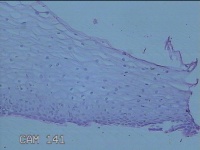

宫颈5点组织

性别

女

年龄

32岁

临床诊断

宫颈上皮内肿瘤,Ⅰ级

一般病史

发现宫颈上皮内瘤变一个月。

标本名称

大体所见

灰白粉红色组织0.6x0.5x0.2cm一块。